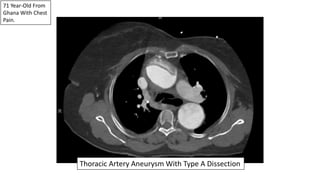

71 Year-Old From

Ghana With Chest

Pain.

Thoracic Artery Aneurysm With Type A Dissection